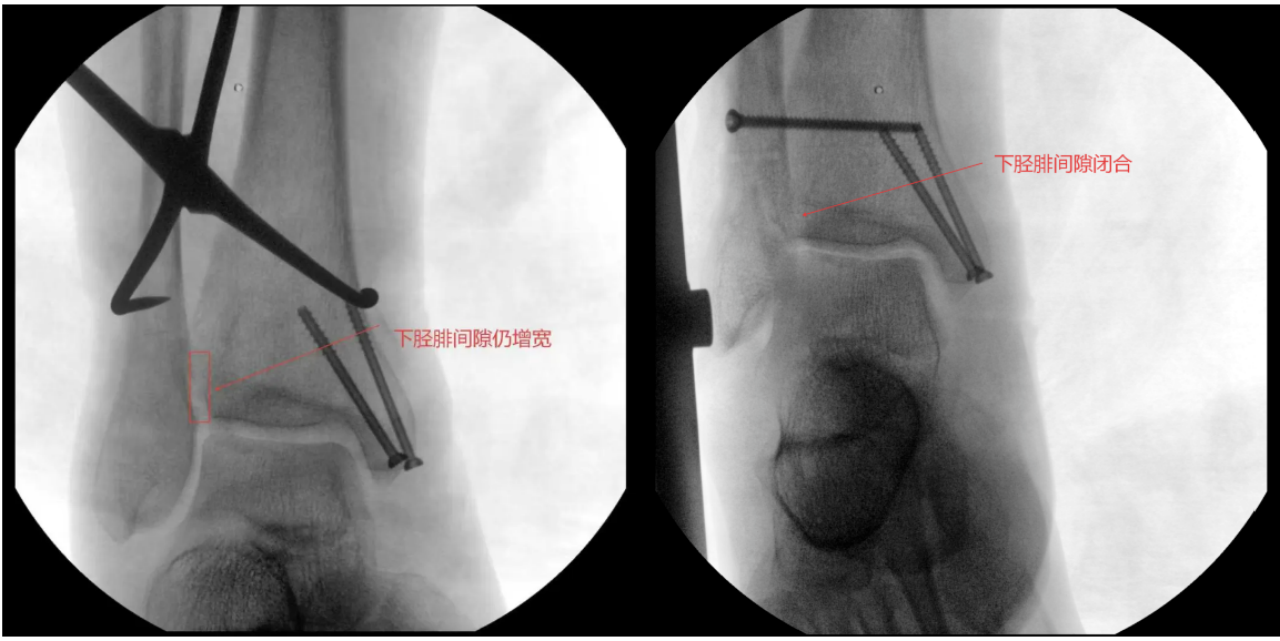

术中进行下胫腓拉力试验结果呈明显阳性,且复位效果未达预期,团队当机立断决定切开探查,发现前结节骨折块嵌顿于下胫腓间隙,正是阻碍复位的关键,取出骨折块后顺利完成复位,手术按规范流程顺利结束。